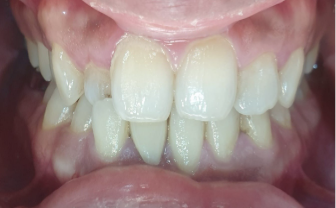

This orthodontic treatment utilized 15 sets of Illusion aligners over a 5-month period. Illusion aligners were crafted from advanced materials making them invisible during wear. These aligners were designed to gradually reposition the upper right lateral incisor and align the lower anterior teeth, keeping the treatment objectives in mind.

Throughout the treatment, one refinement phase was needed. This was done to achieve a symmetric overjet and overbite.

The orthodontic treatment successfully corrected the patient’s anterior crossbite, aligning both upper and lower arches. This intervention resulted in a symmetric overjet and overbite, enhancing his smile aesthetics and overall oral function.

This orthodontic treatment addressed issues concerning the patient using a non extraction approach. Illusion Aligners were delivered to achieve the treatment objectives as it provides aesthetic look and superior quality. The results included successful crossbite correction and alignment of both the arches. The establishment of symmetric overjet and overbite was achieved as well.